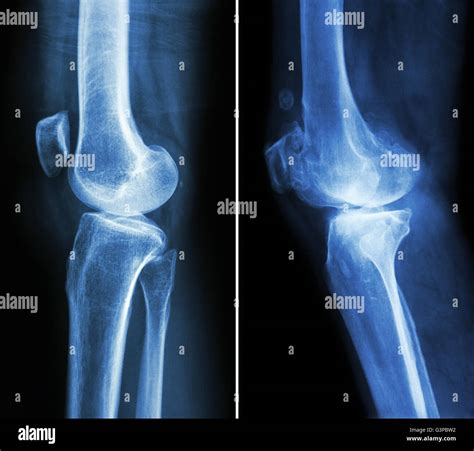

Knee X-rays are a type of medical imaging that uses low doses of radiation to produce images of the knee joint. These images help doctors identify various conditions, including fractures, dislocations, and degenerative changes. The process is non-invasive and relatively quick, making it a preferred method for initial knee evaluations.

• Positioning: You will be positioned on an X-ray table, and the technician will adjust the X-ray machine to capture images from different angles.

Interpreting Healthy Knee X-rays

Interpreting knee X-rays requires a trained eye. Here are some key features that radiologists look for in Healthy Knee X-rays:

• Bone Structure: The bones of the knee, including the femur, tibia, and patella, should appear smooth and intact without any fractures or deformities.

• Joint Space: The space between the bones should be uniform and not narrowed, which can indicate wear and tear or arthritis.

• Alignment: The knee joint should be properly aligned, with no signs of dislocation or misalignment.